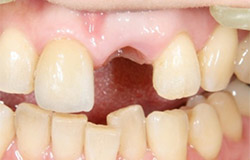

インプラントで噛み合わせの再構成を伴った症例。

治療後のメンテナンスを行わないと

周囲炎になるリスクあり。